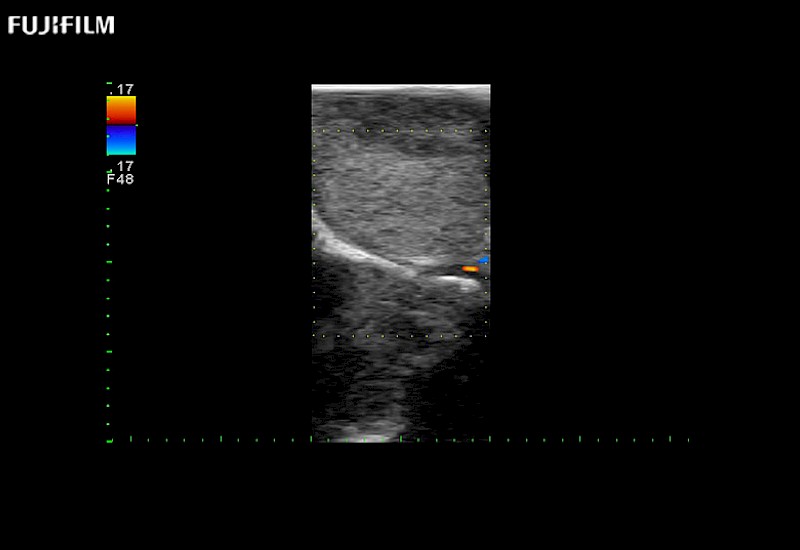

Extraordinary high-resolution digital imaging

Exceptional transducers

Multi-Parametric imaging modalities

Our dedication to neurosurgery allows us to offer superior image quality, outstanding system reliability and intuitive use of cutting edge technology.